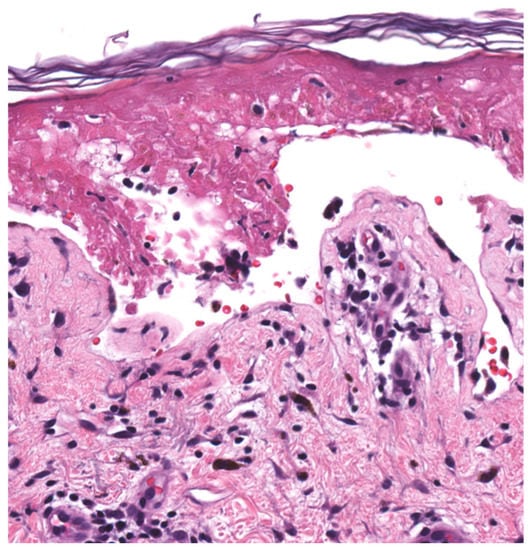

| Histopathology (Figure 2) | Early Stage Basal layer liquefaction with vacuolar interface changes, scattered necrotic keratinocytes, and interface lymphocytes | |

| Late Stage * Subepidermal split with full-thickness epidermal necrosis | ||